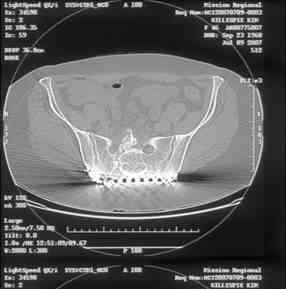

Here is a magnified view. Sorry about the quality but the CT was scanned into our system.

Thank you...it might help to remove the disengaged and other iliosacral screws then insert longer lag screws into the upper sacral segment and if anatomically feasible into the second sacral segment as well.